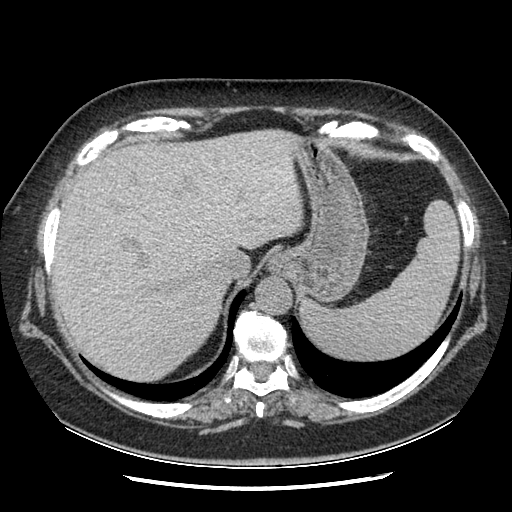

Reconstructed NATIVE CT scan (cycle consistency)

Full window (WL 1023.5, WW 4095 β†’ Low βˆ’1024, High +3071)

Original VENOUS CT scan